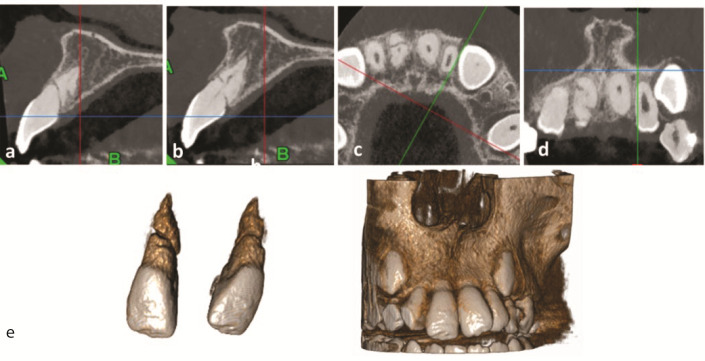

While traumatic injuries in the young permanent dentition are frequent, root fractures are relatively rare, particularly in immature teeth. This study reports the case of a 7-year-old boy who fell off a bicycle. Radiographic examination showed an immature right upper central incisor with fractures in the middle and along the root in an oblique and horizontal direction. Furthermore, there was an extrusion of the coronal segment from its original position. At the first appointment, the right central incisor was repositioned, and a semi-rigid splint was applied for four weeks. The patient was examined periodically for the following two years. After two months, the injured tooth was asymptomatic, with a reduction in probing depth from 8 mm to 2 mm along the tooth surface and a physiologic mobility. Although the injured tooth responded to the electric pulp test after nine months, it had no response to the cold test even after two years. The injured tooth showed continued root maturation of both coronal and apical fragments, although metamorphosis calcification and root canal narrowing were observed in conjunction with mild yellow crown discoloration. This report highlights the ability of Hertwig's epithelial root sheath and immature pulp to continue root development in fractured immature teeth.